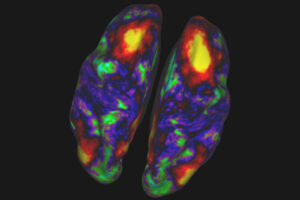

![One February 25, 2015, Lori DeMoe McIntyre died of Alzheimer’s disease at age 56, after participating in DIAN research for nearly eight years. Her daughter Jessica McIntyre memorialized her mom with a large tattoo of Lori’s amyloid PIB PET scan. The younger McIntyre and one of her sisters participate in DIAN and DIAN-TU. [Courtesy of Jessica McIntyre, art by Joey Borger, Certified Customs, Denver, Colorado.]](https://neurology.wustl.edu/app/uploads/2022/06/image-17-300x210.png)